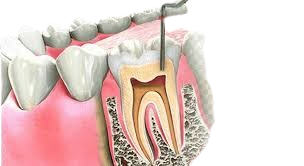

Root Canal treatment

Save your natural tooth with a painless root canal treatment. Ideal for treating deep cavities and infections, ensuring long-term dental health and pain relief.

Saving Smiles, One Root Canal at a Time – DentalEsthetix, Ghaziabad

When it comes to toothaches that just won’t quit, there’s often one lifesaving solution behind t...